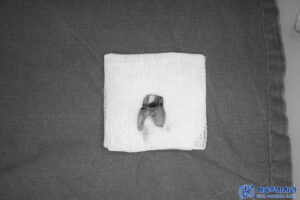

먼저 기존 크라운 제거 후

내부를 확인해 보니

전체적으로 충치가 심하여

발치를 진행하였습니다.